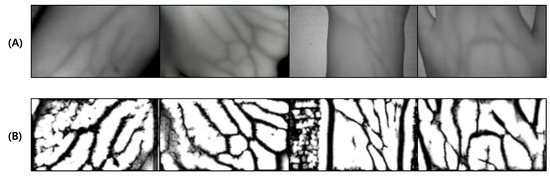

This test was conducted to verify the performance of the proposed vein image processing algorithm itself. Figure 18D was obtained based on the original image without body hair noise, and the performance of the proposed algorithm was verified with a total of 10 images.

Figure 18.

Image operation results without body hair noise: (A) is a test image created for algorithm verification, and (B) is an artificial blood vessel layer used to create the image. (C) is the resultant image of the proposed vein image processing algorithm, and (D) is the resultant image of the Veinvu-100 algorithm.

As a result of the test, in Figure 19C, output by the proposed algorithm, and in (D), output by the VeinVu-100 algorithm confirm the extent to which the path and thickness of the vein can be clearly identified. However, in the case of (C), the brightness of non-venous locations was significantly different from that of veins, and overall, noise was reduced. This makes it easy to grasp the length and thickness of the vein at a glance.

Figure 19.

Results of applying SSIM to the results of the proposed and Veinvu-100 algorithms: (A,B) are binary images of the results of applying the proposed and Veinvu-100 algorithms, respectively, and (C,D) are results of comparing (A,B) with the vessel layer using SSIM.

In the case of the original image (A), it can be seen that the histogram is relatively crowded due to the imbalance of lighting and weak contrast between each component. However, in the proposed algorithm (C), only vascular details with apparent differences were obtained by enhancing the visibility of blood vessels and removing noise components. Therefore, when confirmed with a histogram, it has a form similar to (B). In the case of (D), the contrast with the blood vessels was improved by weakening the vital noise component through image processing, and the blood vessels were captured generally because there was no body hair. However, the histogram has various contrast ratios due to noise detected from components other than blood vessels.

For objective performance verification between the proposed and Veinvu-100 algorithms, SSIM-based similarity evaluation was performed using the output images of each algorithm.

As a result of examining the similarity for all 10 images used in the test, the average similarity of the proposed algorithm was 86.52%, and that of the VeinVu-100 algorithm was 81.48%, indicating that the proposed algorithm improved performance by 5.04% compared to VeinVu-100. Detailed verification results can be seen in Figure 20 and Table 4 below.